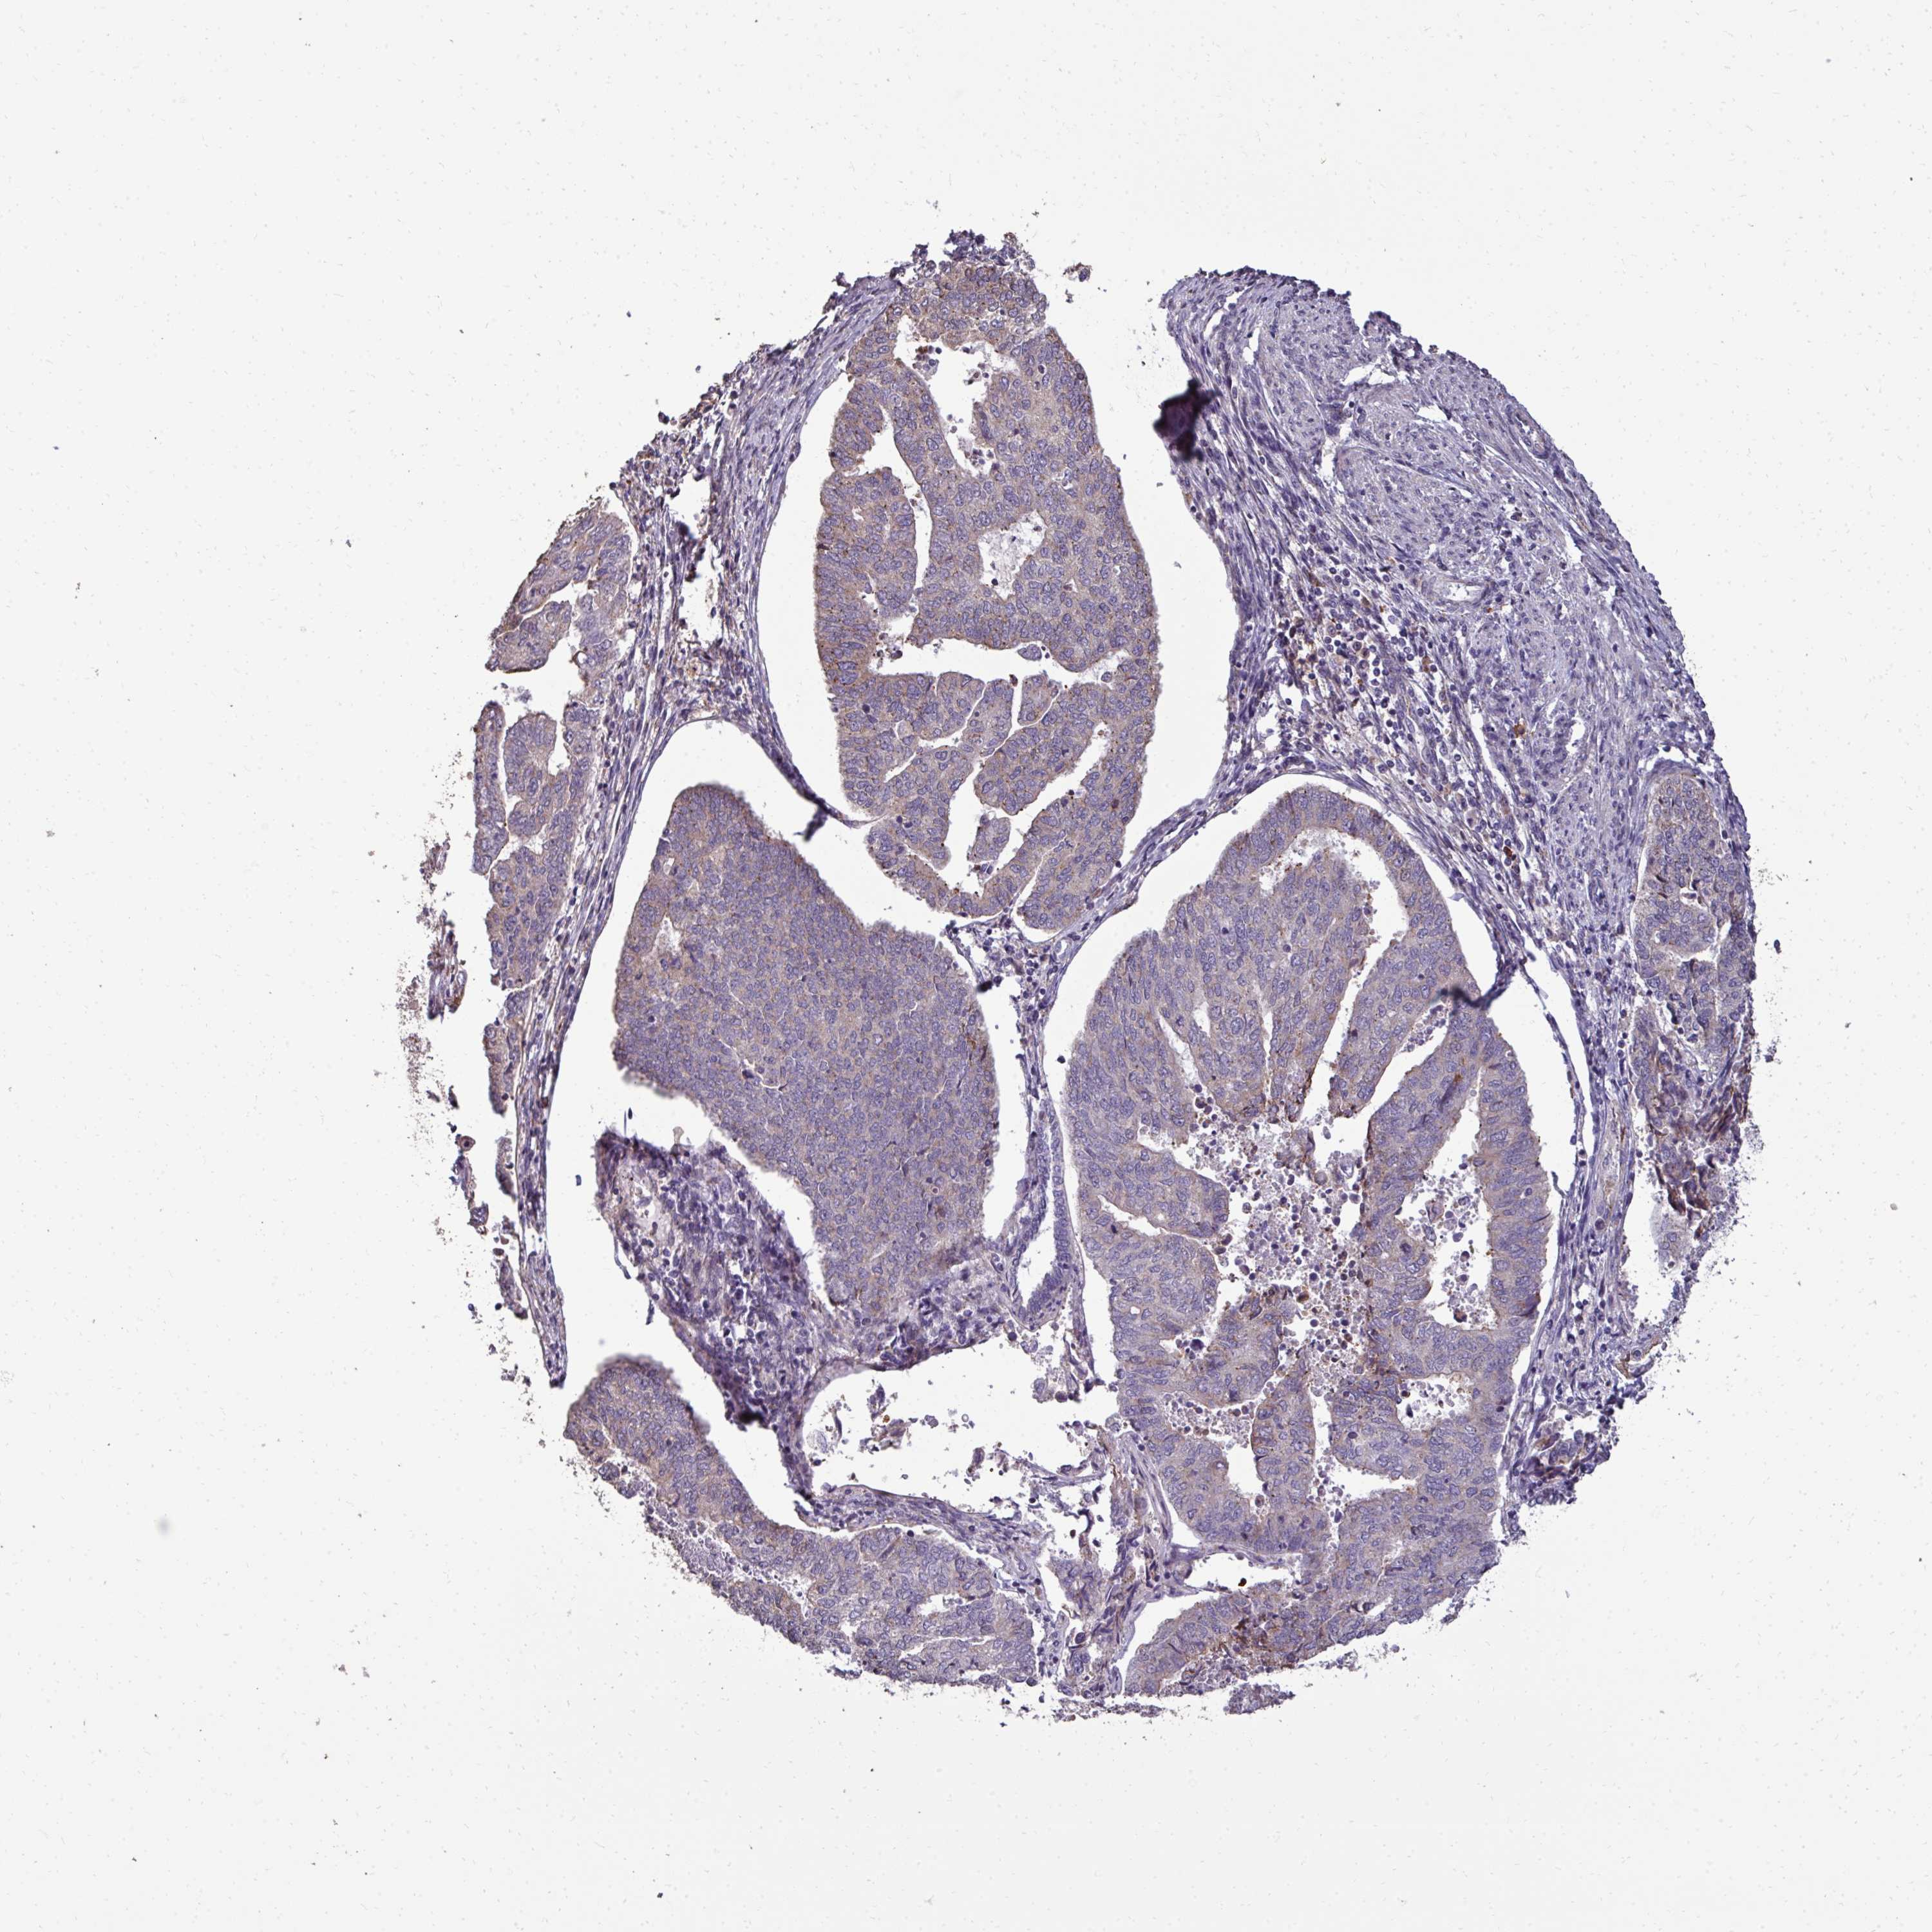

ENDOMETRIAL CANCER - Protein expressioni

A mouse-over function shows sample information and annotation data. Click on an image to view it in a full screen mode. Samples can be filtered based on level of antibody staining by selecting one or several of the following categories: high, medium, low and not detected. The assay and annotation is described here.

Note that samples used for immunohistochemistry by the Human Protein Atlas do not correspond to samples in the TCGA dataset.

Antibody stainingi

Antibody staining in the annotated cell types in the current human tissue is reported as not detected, low, medium, or high, based on conventional immunohistochemistry profiling in selected tissues. This score is based on the combination of the staining intensity and fraction of stained cells.

Each image is clickable and will lead to virtual microscopy that enables deeper exploration of all samples and also displays staining intensity scores, fraction scores and subcellular localization as well as patient and tissue information for each sample.

Antibody HPA055353

Staining

High

Medium

Low

Not detected

Intensity

Strong

Moderate

Weak

Negative

Quantity

>75%

75%-25%

<25%

None

Location

Nuclear

Cytoplasmic/membranous

Cytoplasmic/membranous,nuclear

Adenocarcinoma, NOS